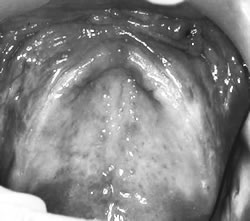

歯科のかかわりで、しっかり噛めるようになりアルブミン値も改善。線維腫を摘出、義歯製作

写真

術前

術後

対象患者さんは自分の歯で充分な咀嚼ができる人は約1割のみで、残りの約9割が充分な咀嚼をするには義歯が必要な人です。その約半数は、義歯使用上の問題を抱え、うまく噛めない人でした。 60 代の男性は上下無歯顎で、上顎義歯が不安定で外れやすく、咀嚼障害がありました。上顎歯肉部には、これまでの不適合義歯により「ビラビラした歯ぐき(線維腫)」ができていました。この浮動性の歯肉が、義歯の安定性と吸着力を阻害した原因でした。歯科では、不適合義歯を調整し、線維腫の摘出と歯肉の形態修正手術を行いました。その後、新しい義歯を製作しました。その結果、食事介助も円滑になり、摂取量も増えました(写真)。